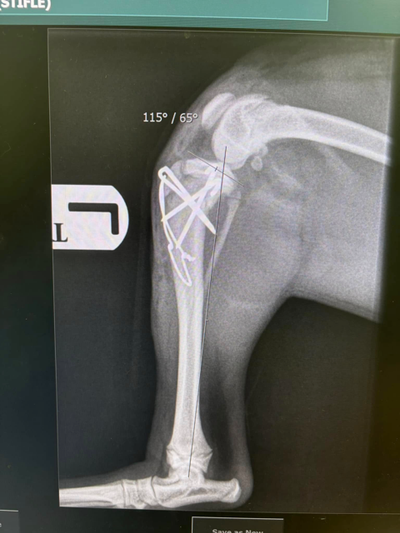

Revision Surgery Post Failed TPLO

In this field is important not only to be able to perform surgery , but to deal with problems when they arise. We performed Revision surgery with Orthogonal platting , restoring normal limb function Surgeon - Andre Pereira